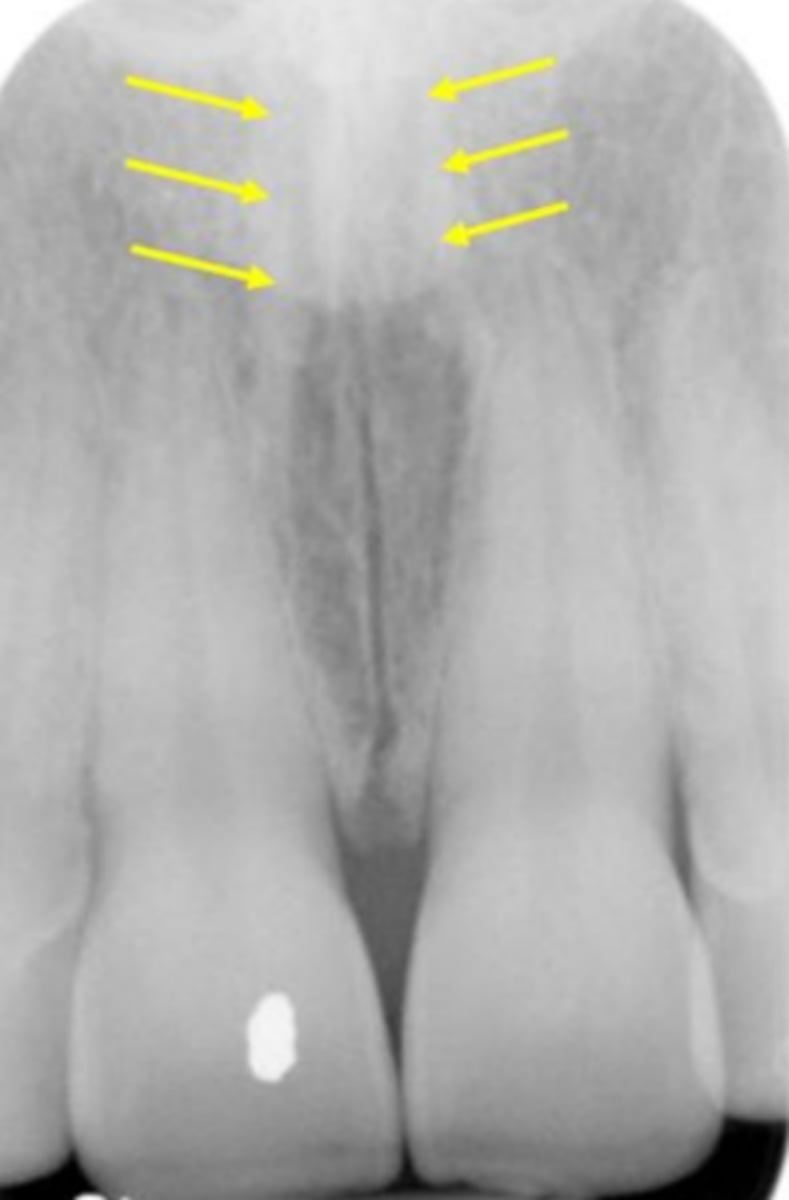

Intermaxillary suture (palatine suture)

Identify the structure

Nasopalatine canal

Superior foramina of the Nasopalatine canal

What is the wide, vertical structure indicated by the arrows?